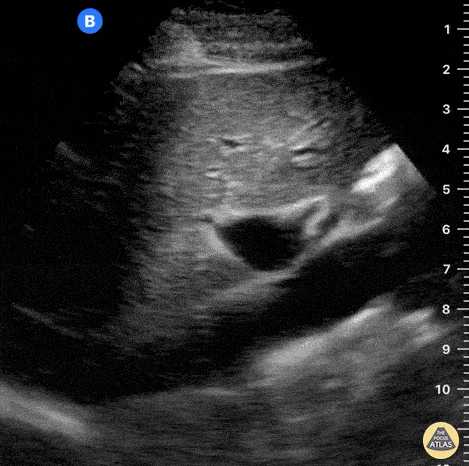

While maintaining its orientation, the probe is dragged to the left of the patient, revealing the abdominal aorta (AA) and the emergence of the coeliac trunk. Notice the contractile, thicker aortic walls and how both the common hepatic artery and splenic artery form the “seagull sign”. Also notice that a normal IVC frequently demonstrates transmitted pulsations from the RA; hence, pulsation is not the proper method for differentiating it from the aorta. This clip is taken over the subxiphoid region, longitudinally to the body’s axis, and with the probe marker oriented to the patient’s head. Dr. Felipe Urriola P., Emergency Unit, Puerto Aysen Hospital, Chilean Patagonia.